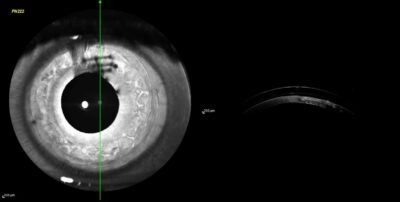

Sklerallinsenanpassung bei Keratokonus mit Myoring

Ein Patient hatte ein intrakorneales Ringsegment in Form eines „Myorings“ aufgrund einer Keratokonus-Ektasie-Erkrankung implantiert bekommen. Der Patient leidet unter starken visuellen Beschwerden wie monokularen Doppelbildern und starken Halo-Lichterscheinungen bei Dämmerung und bei Nacht. Nach erfolglosen Anpassversuchen mit weichen und formstabilen Keratokonus-Kontaktlinsen wünschte der Patient eine Versorgung mittels einer Skleral-Kontaktlinse. Die Sehleistung am betroffenen Auge konnte damit von 20% auf 80% gesteigert werden und die monoklaren Doppelbilder waren aufgrund der Sklerallinse nicht mehr existent.